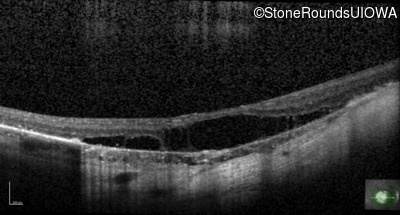

Optical Coherence Tomography - Right - 20/125 +1

Exemplar / OCT Stack

OCT Stack